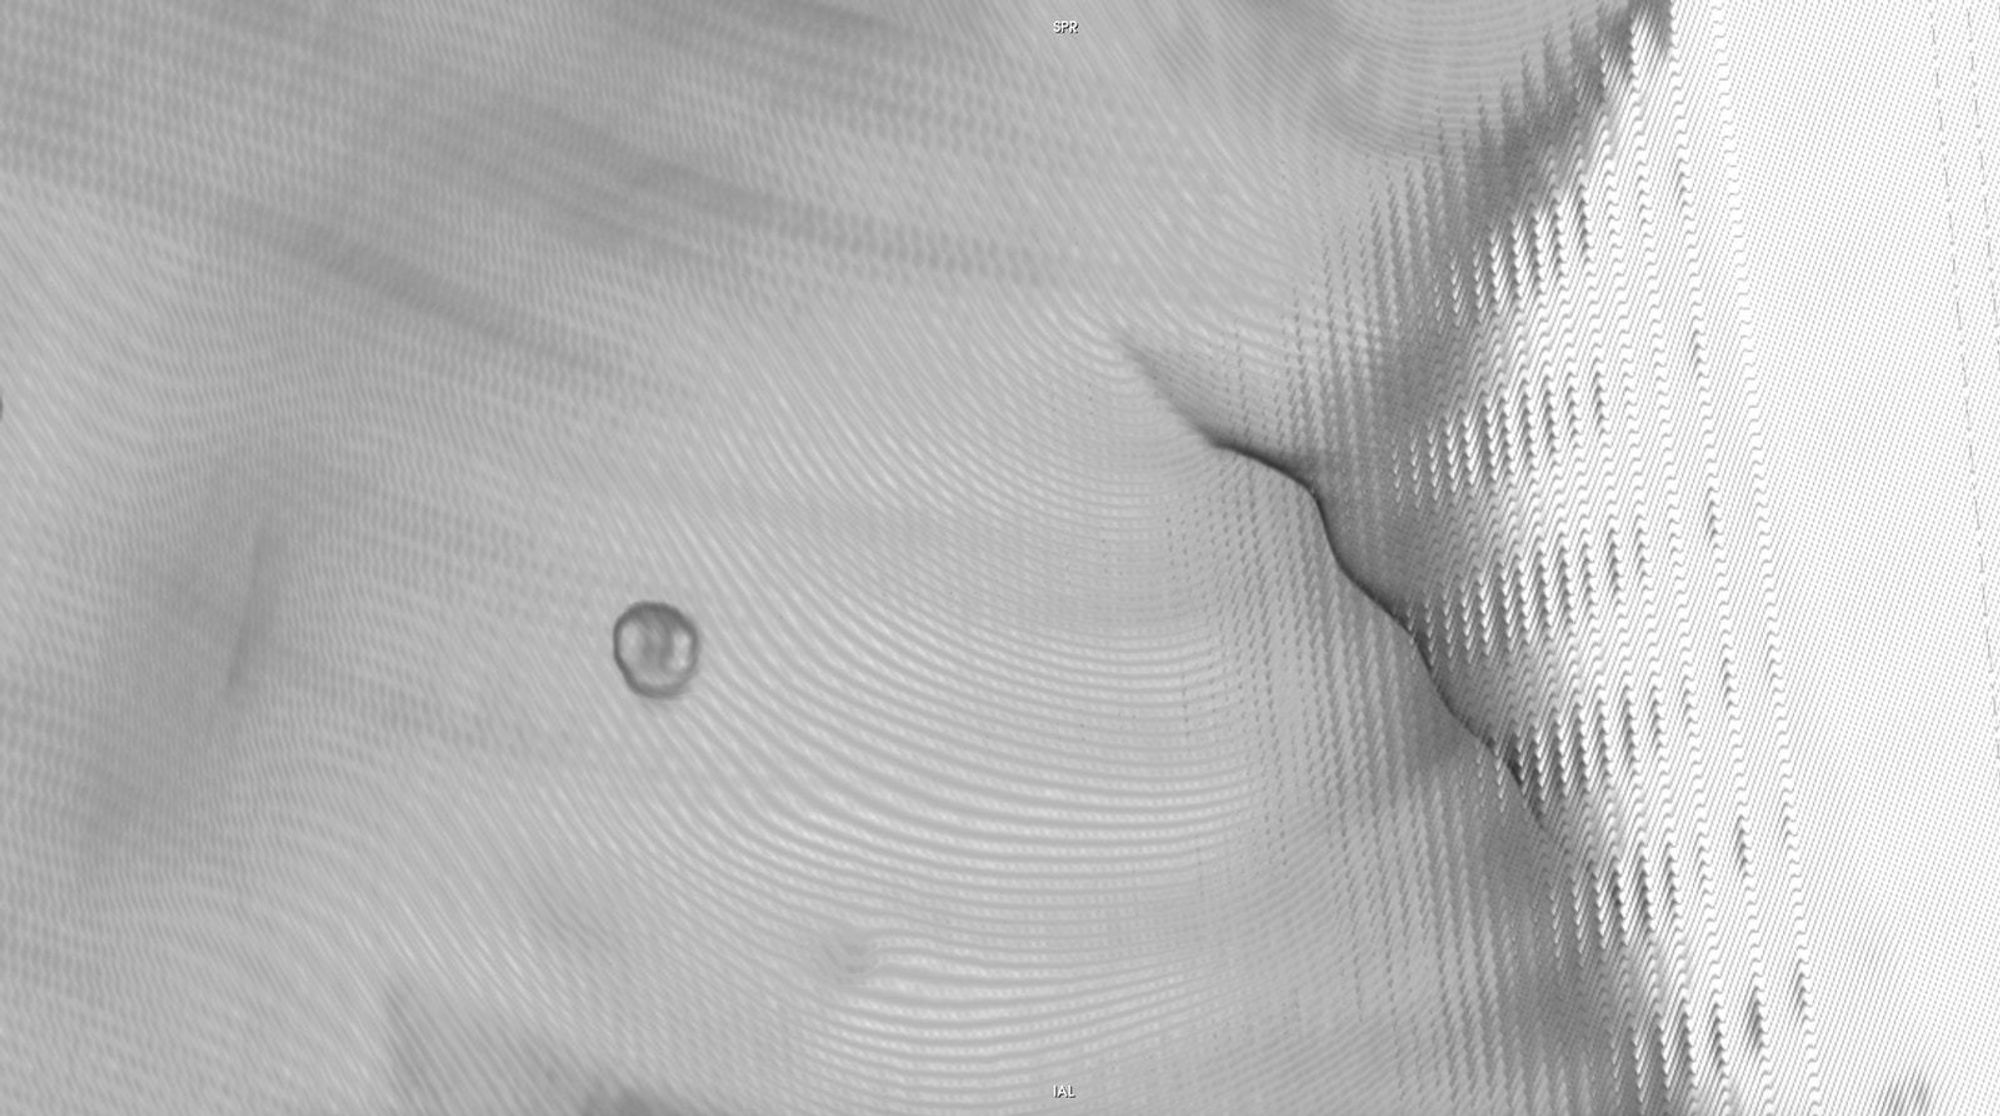

Chasing Intensities considers the body through its relationship to contemporary medical imaging technologies.

The history of medicine can be understood as an on-going endeavour to comprehensively visibilise the body, to pull it from obscurity, to open it out to vision. ‘The x-ray image, with its simultaneous view of the inside and outside, turned the vantage point of the spectator-subject inside out.’ * With the invention of the x-ray, the surface of the body, and its distinction from the world, was dissolved and lost in the image.

In this project, I look at the visual limit between the inside and the outside, the inner and the outer. I combine different visual approaches to materialise the body, using medical imagery, photography from manuals and radiology software. Decontextualised from their origin, these images speak of medicine’s relationship to both sex and violence, and remind us that, in medicine, to go into the body is always to go into the image first.